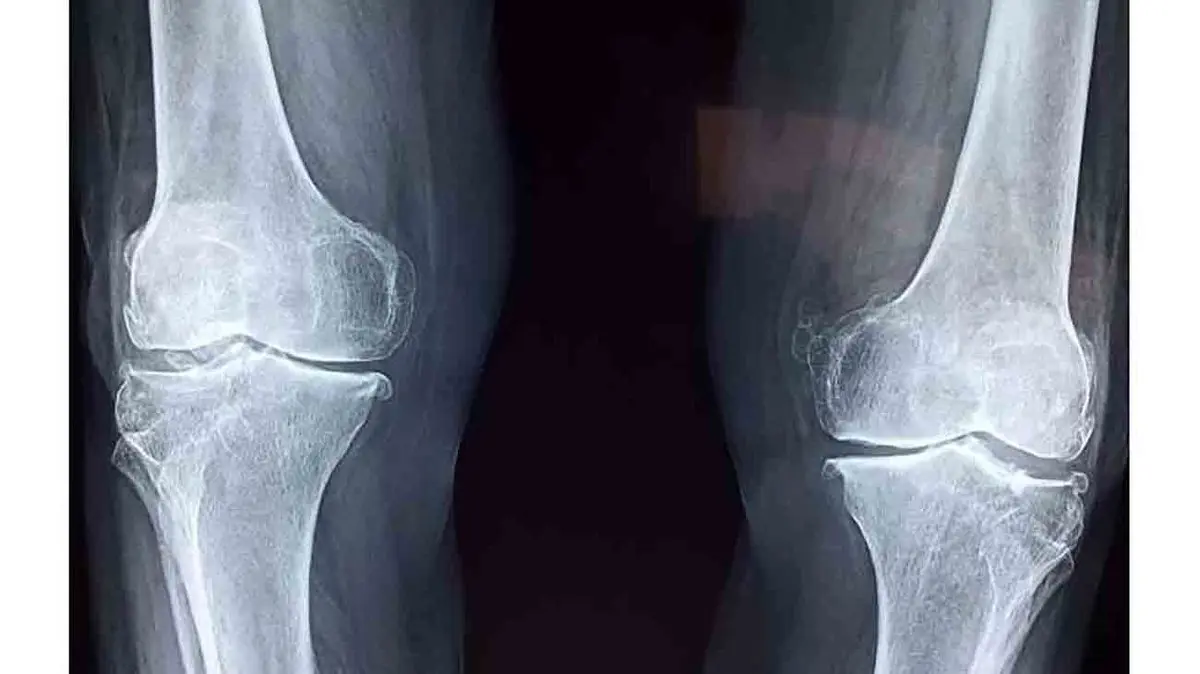

درمان آرتروز زانو با یک تزریق ساده

محققان دانشگاه پنسیلوانیا واقع در آمریکا راهکار جدیدی را برای درمان آرتروز شناسایی کردند که در آن با انجام یک تزریق ساده به مفصل زانو میتوان عوارض این بیماری را متوقف کرد.

به گزارش رکنا ، در این تحقیقات که با استفاده از موشها انجام گرفت، محققان یک مسیر پروتئینی خاص موسوم به گیرنده فاکتور رشد اپیدرمی را شناسایی کردند که با تحریک بیش از اندازه آن میتوان مانع تخریب غضروف مفاصل در طول زمان شد.

این مسیر پروتئینی با سیگنالدهی موجب تولید غضروف در مفصل زانو میشود و تحریک آن با استفاده از مولکولی موسوم به لیگاند موجب شکلگیری غضروف حجیمتر در مفصل و در نتیجه مقاومت بیشتر آن در برابر فرسایش ناشی از بیماری آرتروز میشود.

محققان با استفاده از نانوذرات توانستند مولکولهای لیگاند را که دارای طول عمر کوتاهی هستند، مستقیما به محل مفصل زانو برسانند و مانع اثرگذاری عوامل محیطی بر آن شوند. بدین ترتیب توانستند مسیر پروتئینی گیرنده فاکتور رشد اپیدرمی را تحریک کرده و مانع تخریب غضروف و درد مفاصل زانوی موشهایی شوند که از طریق جراحی عوارض بیماری آرتروز در بدن آنها شبیهسازی شده بود. محققان امیدوارند با استفاده از این راهکار بتوانند پیشرفت بیماری آرتروز را کاهش دهند و مانع از تخریب عضروف شوند.